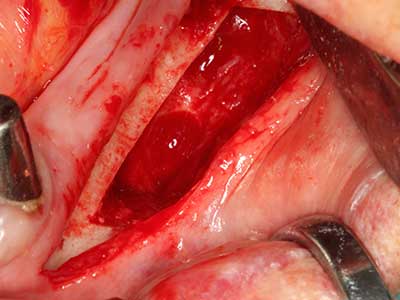

Indication: Bone grafting

Autologous bone transplants are used in the form of blocks, shells, rings and are also combined with bone replacement materials as chips. If the implant site is prepared at the same time as the augmentation, various bone filter systems have proven effective for collecting the resulting bone chips. As an alternative, the implant site can be prepared using a low-speed device without irrigation. If an implant is not inserted, bone chips can be harvested from the periphery with bone scrapers. This is also possible with piezo surgery using specialized attachments that yield higher-quality bone chips compared chips harvested with round drills, as has been confirmed in a study comparing the two methods (Chiriac, Herten et al. 2005).

Piezo surgery has additional advantages when harvesting bone blocks. In addition to the high precision with osteotomy described above, the use of the thin saw tips specifically minimizes loss of material. Greater loss of material during harvesting can be expected with the thicker instrument tips, particularly when using Lindemann drills (Lakshmiganthan, Gokulanathan et al. 2012). The basal separation, which is necessary particularly for retromolar block transplants, is simplified by specially designed rectangular saws, with the result that piezo surgery is viewed as a precise, simple and safe procedure for harvesting retromolar bone blocks (Happe 2007) (Fig. 1-12).